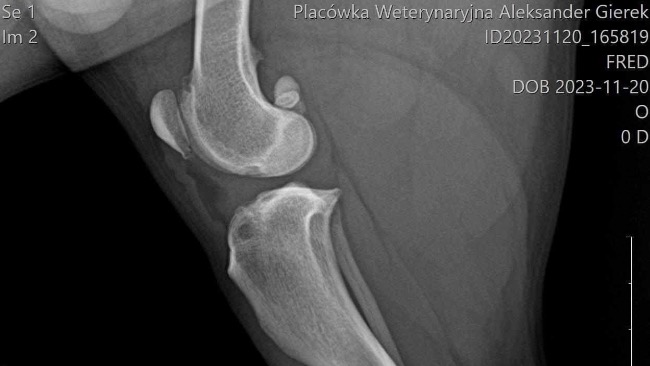

Początkowo pojechalam z partnerem do weterynarza ktory po konsultacj z nami i zbadaniu pieska podejrzewał zerwanie więzadła krzyżowego. Weterynarz skierował nas na prześwietlenie łapki oraz badania krwi do Dr. Gierek w Katowicach. Niestety obawy naszego weterynarz się potwierdziły okazało się ze musi mieć jak najszybszą operacje ponieważ gdy nie zoperujemy zerwanego więzadła piesek będzie cierpiał i jednocześnie obciążał mocno druga tylnią łapkę i może dojść do zerwania więzadła w drugiej łapce a wtedy nasz piesek już nie będzie mógł biegać.

Całą zebrana kwotę przekażemy na operacje naszego psiaka. W załączniku udostępnione są wyniki oraz zdjęcie łapki